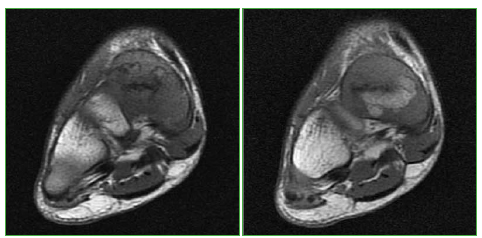

Instrucción Ortopédica de Posgrado - Imágenes. Resolución del caso.

Trueba, R. (2020). Instrucción Ortopédica de Posgrado - Imágenes. Resolución del caso. Revista De La Asociación Argentina De Ortopedia Y Traumatología, 85(2), 184-186. https://doi.org/10.15417/issn.1852-7434.2020.85.2.1076

Instrucción Ortopédica de Posgrado - Imágenes-Resolución

Ricardo Trueba, Departamento de Resonancia y Tomografía Computada, Grupo Médico Rostagno, Diagnóstico por Imágenes, Ciudad Autónoma de Buenos Aires, Argentina